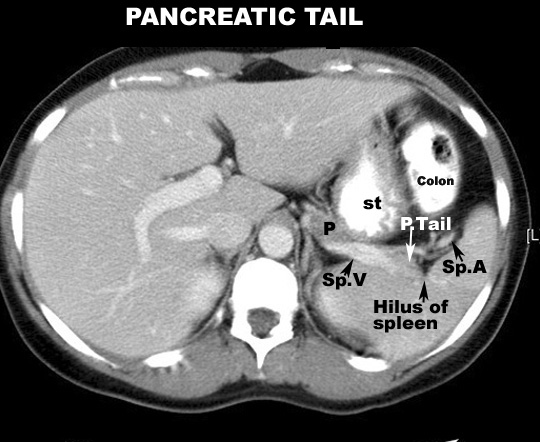

- Tail

- The tail of the pancreas lies in the splenorenal ligament and

enters the hilum of the spleen with splenic vessels.